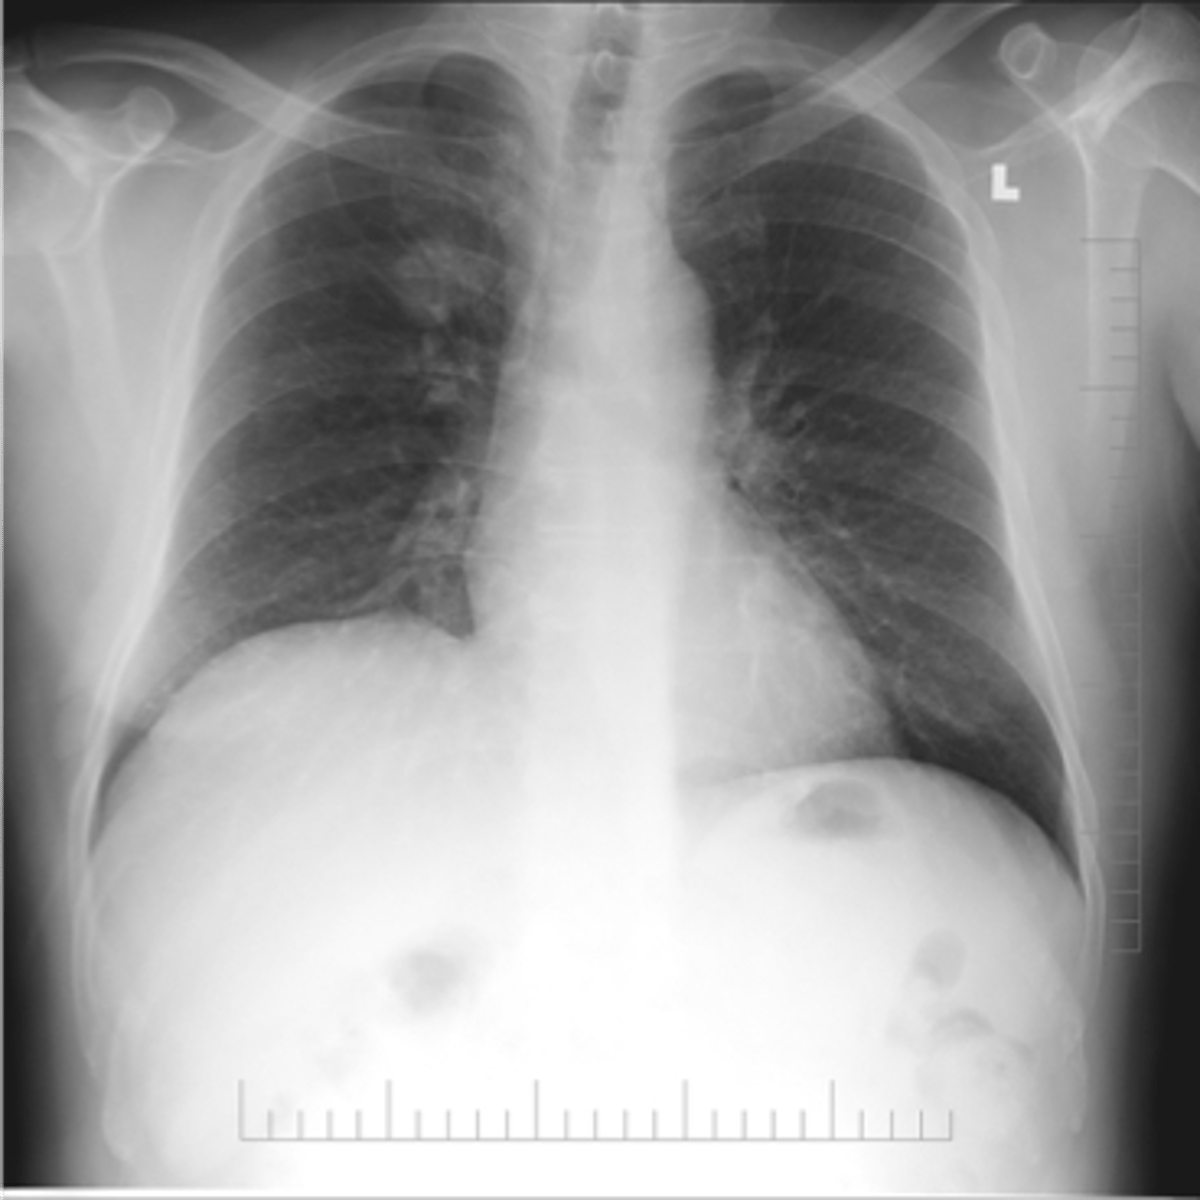

Bilateral interstitial infiltrates

Bilateral pleural effusion